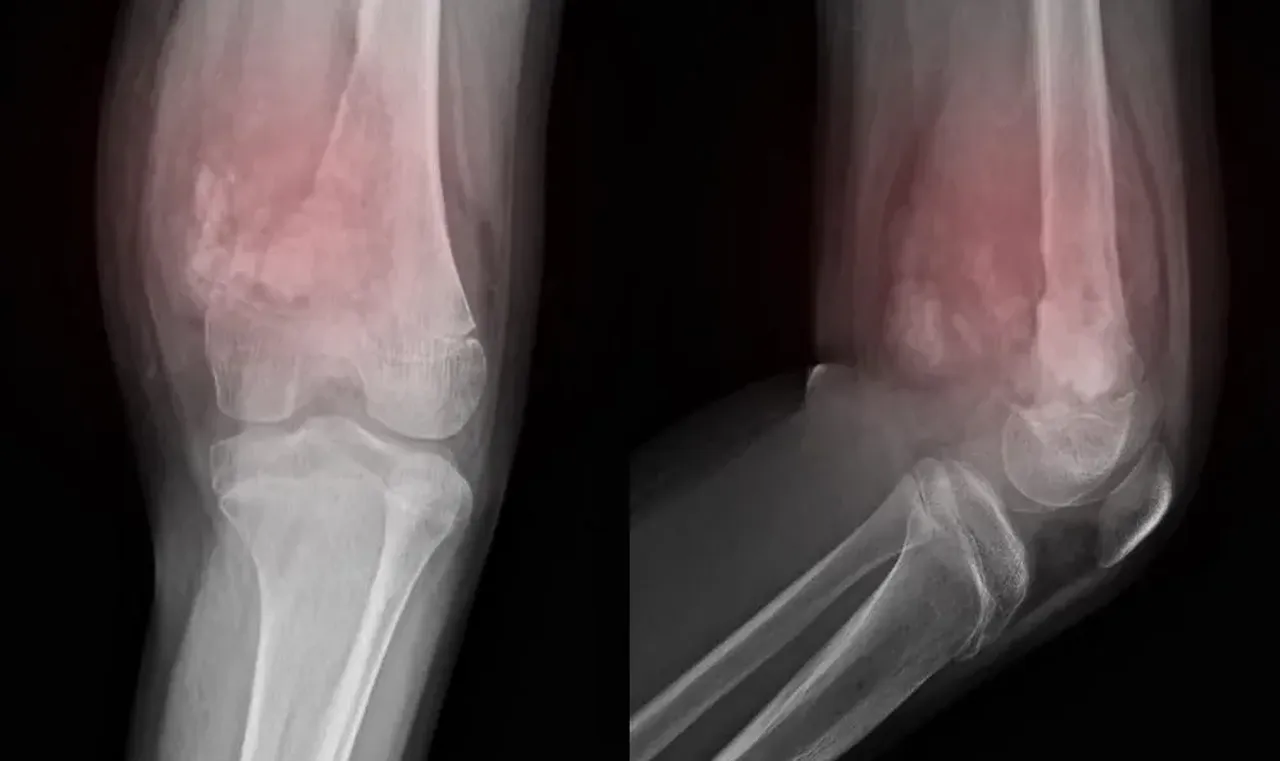

Rabdomyosarkom, kas veya fibröz dokuda gelişen nadir ve agresif bir yumuşak doku kanseridir. En sık 5-9 yaş arası çocuklarda görülür. Uzmanlar, ebeveynlerin çocuklarında fark ettikleri şişlikleri, açıklanamayan yorgunlukları ve mide rahatsızlıklarını ciddiye alması gerektiği konusunda uyarıyor.

Rabdomyosarkom, çocukluk çağında görülen yumuşak doku sarkomlarının en yaygın türüdür.

Erken teşhis edilmediğinde hızla yayılabilir.

Karında görüldüğünde, solunum güçlüğüne kadar ilerleyebilen bası semptomlarına neden olabilir.